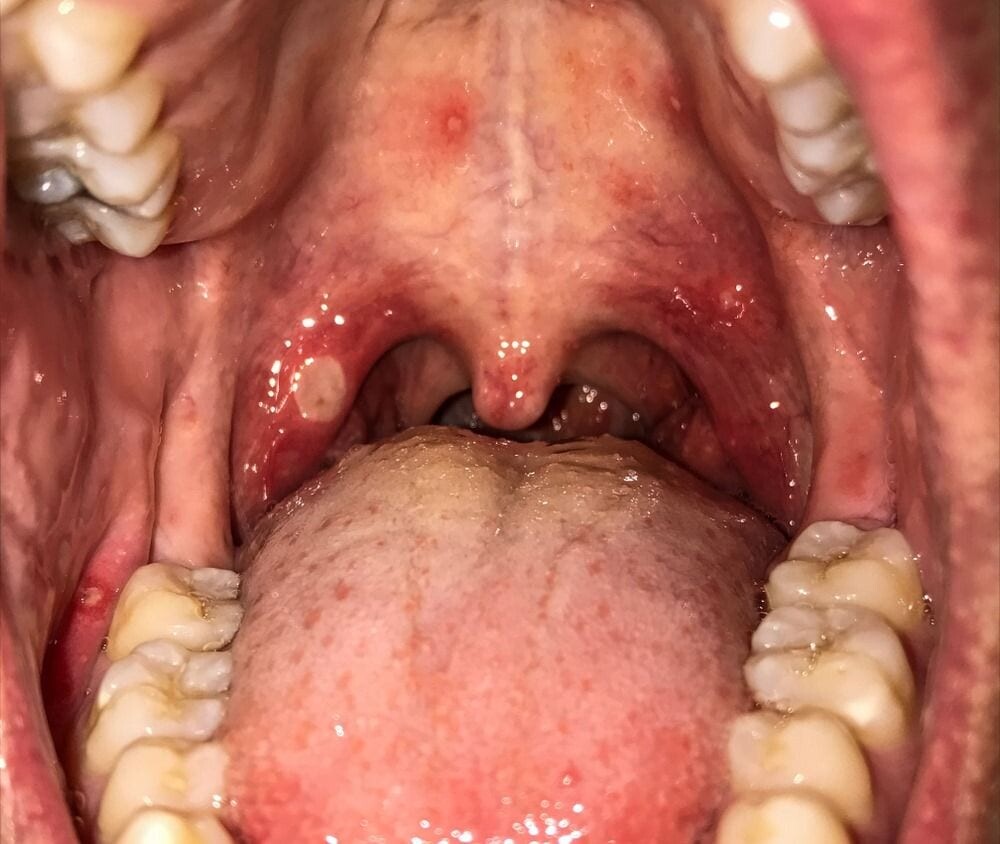

Canker sores are small, painful ulcers that can develop on the hard palate or anywhere on the soft tissues in the mouth. They’re usually white or yellow with a red border and can make eating and drinking uncomfortable.

The lesions may resemble cold sores but don’t occur on the surface of lips and are not contagious.

The herpes simplex virus causes cold sores. If the roof of your mouth hurts and you can see blister patches, they could be cold sores. These mouth sores usually appear on the lips but can also develop on the hard palate.

Small fluid-filled blisters typically erupt along the vermillion border of the lips. These blisters can also appear around the nose, cheeks or inside of the mouth.

The small blisters may merge and then burst, leaving a shallow, open sore.